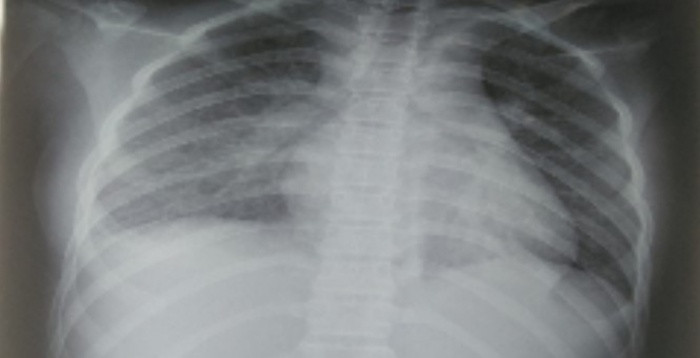

Kết quả các xét nghiệm cho thấy tổn thương nhiều cơ quan, trong đó phổi có tổn thương mờ dạng kẽ vùng rốn phổi 2 bên; tim có tràn dịch màng ngoài tim; tăng chỉ số Troponin T, pro-BNP. Các chỉ số men gan ASAT/ALAT cũng tăng gấp 2 lần. Các chỉ số viêm tăng rất cao, định lượng Interleukin-6 (cytokine viêm) cũng tăng cao.